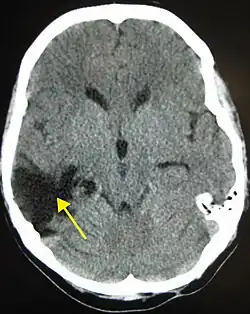

Los hematomas intraparenquimales se encuentran inmersos en la sustancia cerebral y tienden a ocurrir en TCE graves con preferencia sobre los lóbulos frontales y temporales. Estos hematomas se asocian con contusiones del tejido cerebral aledaño. Las hemorragias subaracnoideas son comunes después de un TCE grave y no producen efecto de masa o hematoma y pueden estar asociadas con vasoespasmo postraumático.[15] Un caso especial de hemorragias es la hemorragia de Duret, que tiene lugar en la protuberancia o el mesencéfalo y se asocia con hernia uncal.[15]

Contusiones

Las contusiones se encuentran en 20% al 25% de los pacientes con TCE grave. Son lesiones heterogéneas compuestas de zonas de hemorragia puntiforme, edema y necrosis que aparecen en las imágenes de TC como áreas de hiperdensidad puntiforme (hemorragias), con hipodensidad circundante (edema), suelen estar localizadas en la cara inferior del lóbulo frontal y la cara anterior del lóbulo temporal por su relación con el ala mayor del esfenoides. También se pueden encontrar en la superficie de impacto y en la superficie contraria a este, el llamado efecto golpe-contragolpe. Cuando estas evolucionan se parecen más a los hematomas intracerebrales y su ubicación depende el posible efecto de masa.